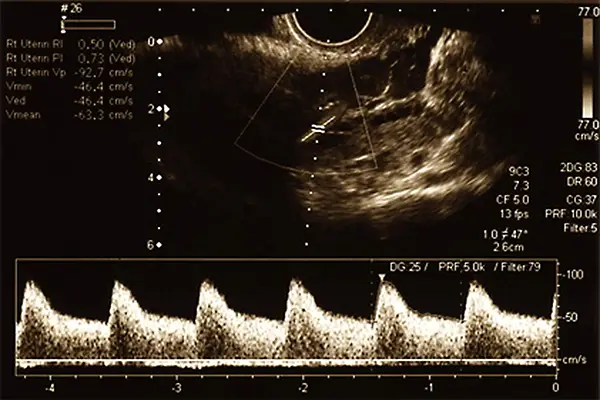

Die Dopplersonografie, eine spezielle Form des Ultraschalls, wird in der Schwangerschaft eingesetzt, um neben den Organstrukturen des Ungeborenen auch die Blutströmung in den Gefäßen zu beobachten. Diese Untersuchung ist für Mutter und Kind völlig ungefährlich und ermöglicht es, den Blutfluss in wichtigen Gefäßen wie der Nabelschnur oder der Gebärmutter zu messen. So können Engstellen oder Unregelmäßigkeiten frühzeitig erkannt werden.

Die Duplexsonografie kombiniert herkömmliche Ultraschallbilder mit der Dopplersonografie und ermöglicht es dem Arzt, sowohl den Blutstrom als auch die Struktur der Gefäßwände gleichzeitig zu beurteilen. Dieses Verfahren bietet eine detailliertere Einsicht und ist besonders wertvoll für eine umfassende pränatale Diagnostik.